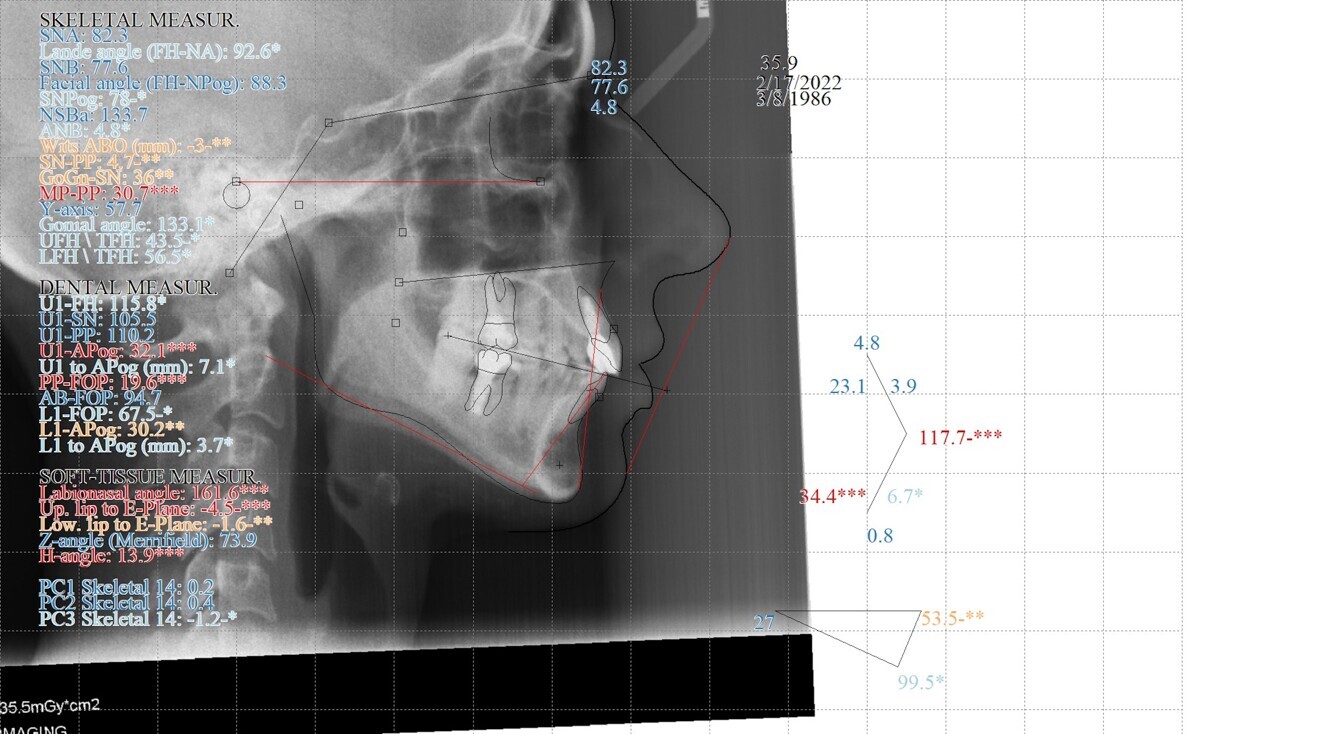

Fig. 4: Pretreatment cephalometric radiograph and analysis.

The third molars were not present. The evaluation of the cephalometric radiograph (Fig. 4) showed a retrognathic mandible (SNB: 74.2°) and normal inclination of the incisors, both maxillary (Ui–FH: 111.3°) and mandibular (Li–APog: 24.2°).

Regarding the final cephalometric analysis, the facial height (LFH: 56.5 mm) and measurements of soft tissue remained the same. The inclination of the maxillary incisors was well preserved (Ui–FH: 115.8°), and the mandibular incisors were slightly proclined (Li–APog: 30°; Fig. 16).

Fig. 16: Final cephalometric radiograph and analysis.